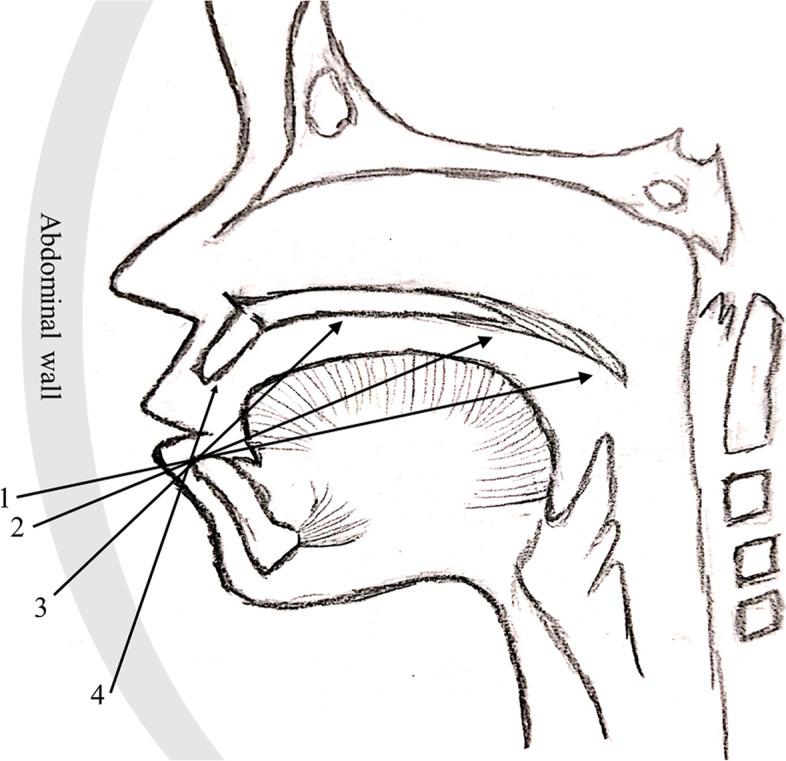

Prenatal diagnosis of cleft palate is still challenging. To describe a practical and efficient method, sequential sector-scan through oral fissure (SSTOF), to evaluate palate.

According to the characteristics of the fetal oral anatomy and ultrasonic directivity, we designed a practical method, sequential sector-scan through oral fissure, to evaluate the fetal palate, and the approach was verified efficiently by following up results of those fetuses with orofacial cleft who were induced because of their accompanied lethal malformations. Then, the 7098 fetuses were evaluated using sequential sector-scan through oral fissure. Fetuses were followed up after birth or induction to validate and analyze prenatal diagnosis.

RESULT

According to the scanning design, sequential sector-scan through oral fissure was performed successfully from the soft palate to the upper alveolar ridge in induced labor fetuses, and the structures were displayed clearly. Among 7098 fetuses, satisfactory images were obtained for 6885 fetuses and the remaining 213 fetuses' images were unsatisfactory because of fetuses' positions and pregnant women with high BMI. Among 6885 fetuses, 31cases were diagnosed CLP or CP, which were confirmed after delivery or termination. There were no missing cases.